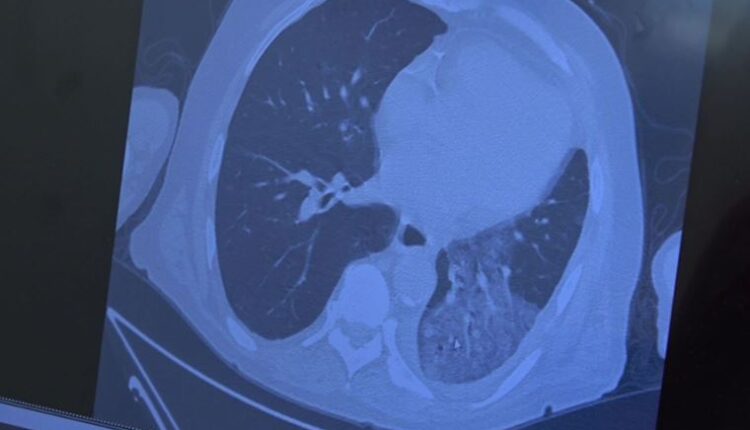

– Bayramdan sonra bir miktar vaka sayılarında artış bekliyoruz. Gerçekten şuan normal vakalar zatürre vakaları seviyesindedir. Artık salgının topluma getirdiği ekstra bir risk yoktur. Alarm durumunda dikkat etme durumuna geçtik. Özellikle bu yurt dışı turlarının etkisiyle bayramla birlikte ve bayramdan sonra vaka artışları bekliyoruz. İnsanlarımızın mevcut aşılarına, mevcut kontrollü sosyal hayatlarına devam etmelerini öneriyoruz. Her ne kadar toplumda şu an yatan hasta sayısı olmasa da özellikle 65 yaş ve üstü hastalarımızda, immün sistemi düşük hastalarımız akciğer tutulumlarıyla gelmeye başladı. Bunun bayramdan sonra artmaması için yaşlılarımızı bayramda ziyaret ederken lütfen onlara kontrollü yaklaşmanızı istiyoruz” diye konuştu.

– Yabancıların bayram nedeniyle ülkelerine gidip gelmeleri nedeniyle ülkemizde bir miktar vaka artışları göreceğiz. Amacımız bu vaka artışların yaşlıların özellikle akciğer tutulumlarını önlemektir. Her ne kadar maske yasağı gevşetilse de her ne kadar aşılanma oranı azalsa da özellikle yaşlılarımızı korumak için dikkat etmenizi istiyoruz” şeklinde konuştu.